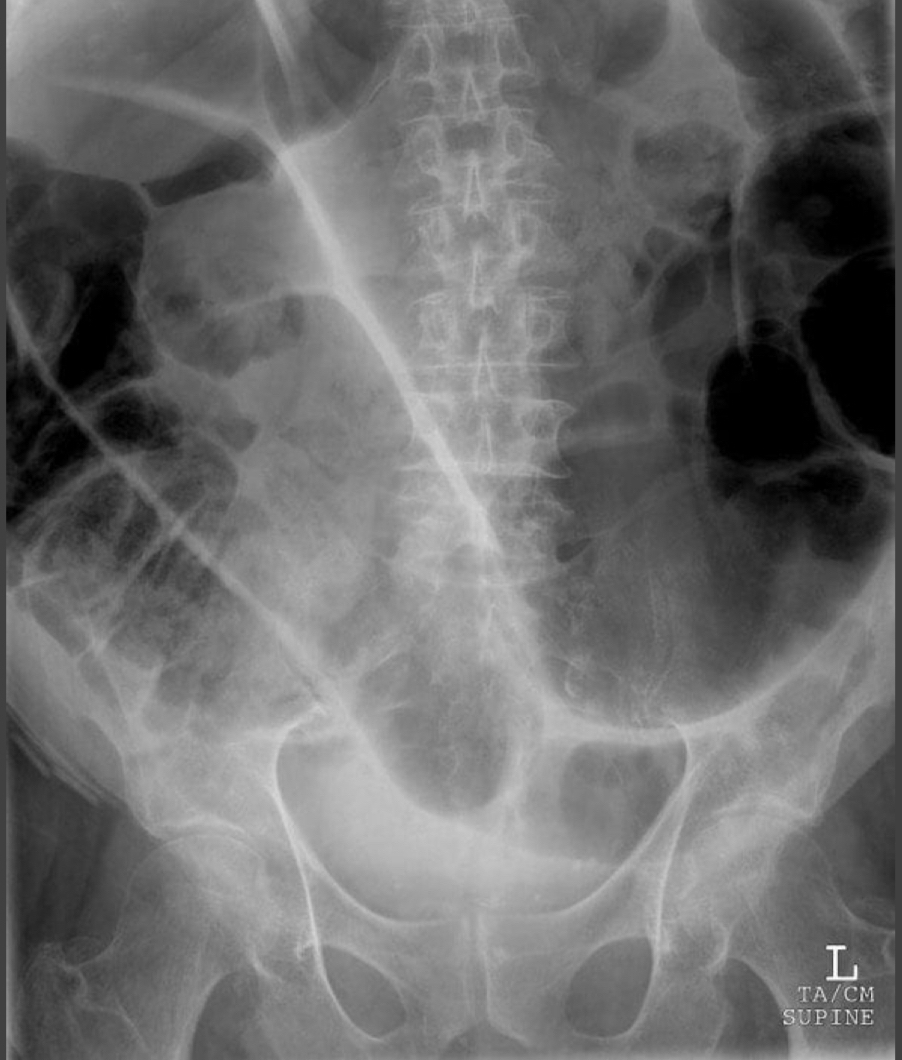

Nasogastric (NG) Tube

Tip should be below diaphragm.

Tip remains left of spine.

Nasoduodenal Tube

Crosses from left to right side of spine.

Advances toward jejunum.